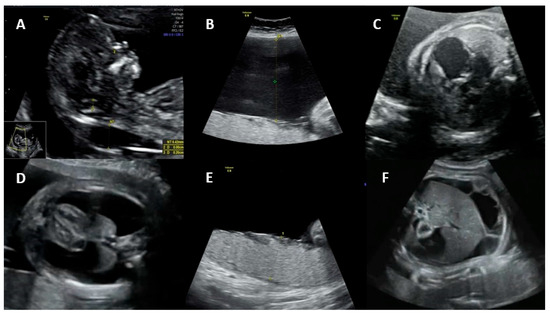

Fetal ultrasound signs associated with hydrops include ascites, skin edema, pleural and pericardial effusions, and placental edema. Possible mechanisms for the development of hydrops are (1) fetal anemia due to the virus crossing the placenta and infecting erythrocyte precursors in the fetal bone marrow, associated with a shorter fetal erythrocyte half-life (especially during the hepatic stage of hematopoiesis), contributing to severe anemia, hypoxia, and high-output heart failure; (2) fetal viral myocarditis resulting in heart failure and impaired liver function due to direct damage to hepatocytes and indirect damage from hemosiderin deposition [25,28,30]. Spontaneous improvement of fetal hydrops may occur in approximately 34% of cases by the time of delivery [35]. Figure 1 shows the main ultrasonographic findings of intrauterine parvovirus B19 infection.

Figure 1.

Main ultrasonographic findings of intrauterine parvovirus B19 infection: (A) increased nuchal translucency, (B) polyhydramnios, (C) cardiomegaly, (D) pleural effusion, (E) placentomegaly, and (F) ascites.